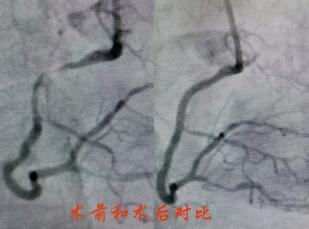

造影提示陶奶奶冠脈病情較重,左主干+三支病變,屬于非常復(fù)雜也極為危險(xiǎn)的冠脈病變。經(jīng)過(guò)心內(nèi)科介入團(tuán)隊(duì)和家屬的反復(fù)溝通,立即對(duì)陶奶奶的右冠進(jìn)行了支架置入,術(shù)后陶奶奶的胸痛很快緩解,并經(jīng)過(guò)數(shù)天的后續(xù)治療,順利出院。

春節(jié)剛過(guò),陶奶奶的孩子們帶著陶奶奶再次來(lái)到了江寧中醫(yī)院心內(nèi)科準(zhǔn)備拆除這顆潛在的“致命炸彈”。韋鋒主任反復(fù)研究陶奶奶的前期手術(shù)影像,心中擬定著多個(gè)手術(shù)方案。經(jīng)過(guò)充分準(zhǔn)備,2月15日,韋鋒主任再次為陶奶奶進(jìn)行了介入手術(shù)。術(shù)中通過(guò)血管內(nèi)超聲(IVUS)精細(xì)、準(zhǔn)確評(píng)估陶奶奶的冠脈病變情況,發(fā)現(xiàn)陶奶奶的左主干最小管腔面積僅僅3.7mm2,;前降支近段全程鈣化,最嚴(yán)重處呈270度的環(huán)形鈣化,最小管腔面積僅僅2.1mm2;回旋支開(kāi)口正常,回旋支近端最小管腔面積1.8mm2。韋鋒主任根據(jù)IVUS的結(jié)果,改變了原來(lái)擬定的DKCRUSH術(shù)式,決定采用藥物球囊和藥物涂層支架相結(jié)合的方式處理病變(LCX藥物球囊,LM-LAD植入支架),經(jīng)過(guò)近2個(gè)小時(shí)的手術(shù),陶奶奶的冠脈血管又“完美”地回來(lái)了。